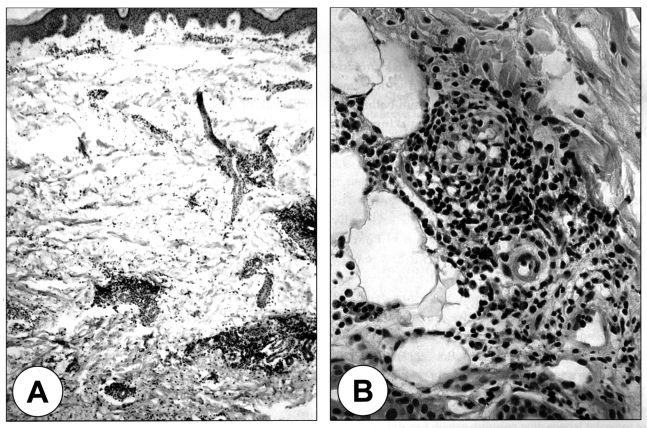

The laboratory findings revealed an increased number of WBC (19,060/mm3) with a normal eosinophil count and normal serum IgE level. A stool examination showed no eggs of the parasites and the chest X-ray was within the normal limits. A pathological examination on the biopsied specimen showed only dermal patchy infiltrations of lymphocytes and eosinophils, and neither the worm section nor evidence of tunnel formation by the migrating larvae were found (Fig. 2). The patient s serum was serologically negative by multiple-dot ELISA using 12 parasite antigens: they were Dirofilaria immitis, Toxocara canis, Ascaris suum, Anisakis simplex, Gnathostoma doloresi, Strongyloides ratti, Paragonimus westermani, Paragonimus miyazakii, Fasciola hepatica, Clonorchis sinensis, Spirometra erinacei, and Cysticercus cellulosae. However, by microplate ELISA using antigens of G. doloresi and A. caninum, the patient's serum showed positive reaction against the antigen of A. caninum, but did not against Gnathostoma antigen (Table 1). Therefore, he was serologically diagnosed with cutaneous larva migrans caused by a larval infection of A. caninum. After an oral treatment with 400 mg/day of albendazole for three days and ivermectin at a single dose of 150 µg/kg, the skin lesions resolved without recurrence after a follow up period of 6 months.